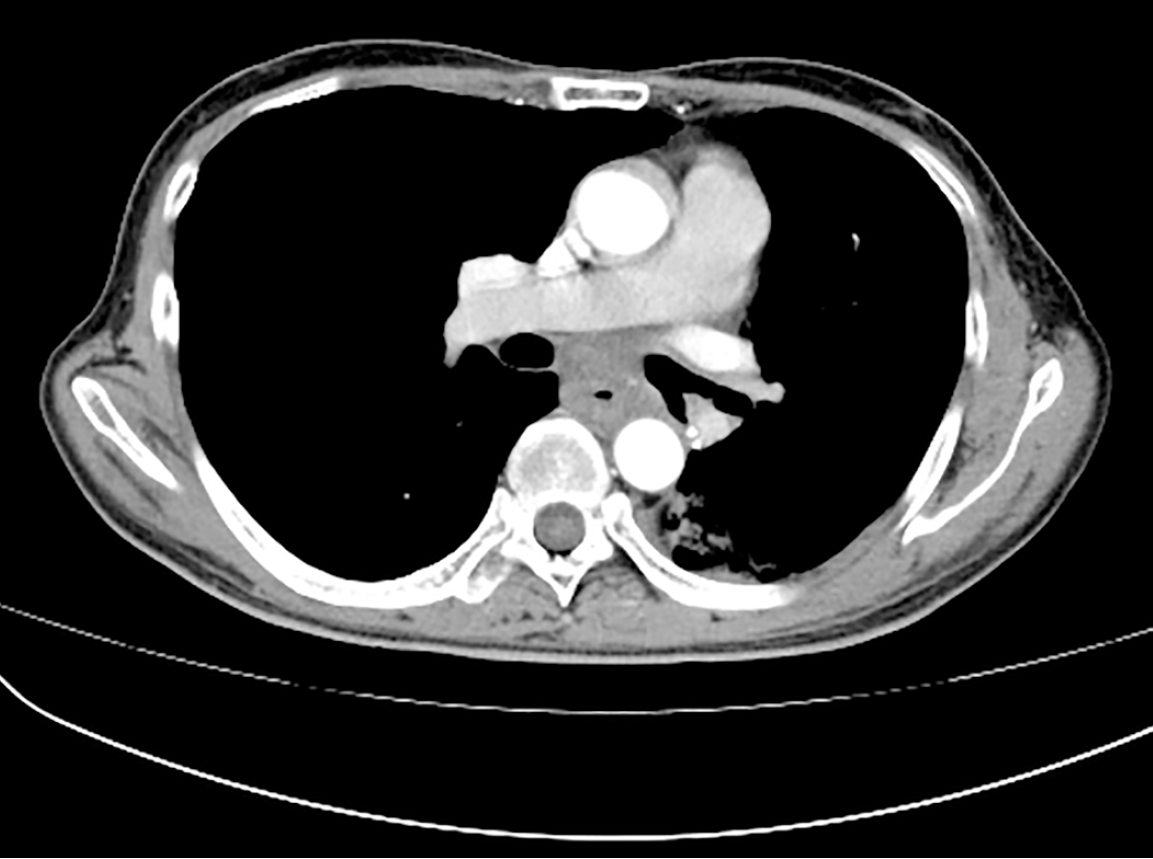

Figure 3 Chest computed tomography imaging.

A: Showing mid-esophageal wall thickening and subcarinal lymphadenopathy when the patient presented to the thoracic surgeon; B: Showing the volume of the esophageal tumor increased, causing the esophageal lumen to narrow, after two cycles of neoadjuvant immunochemotherapy.